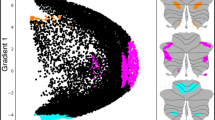

In this work, we shift the focus from structural neuroplasticity to functional neuroplasticity, and from localized analysis to whole-brain analysis. Via the fully automated independent component analysis (ICA) framework [E-Field modeling The Simulation of Non-Invasive Brain Stimulation (SimNIBS) toolbox was used for E-field modeling to generate a subject-specific anatomically realistic volume conductor model [35]. Via a combination of the FSL toolbox and the SPM 12 toolbox, T1- and T2-weighted images were segmented into skin, bone, eyes, cerebral spinal fluid, ventricles, and gray and white matter. The segmented tissue compartments were meshed into a head model using Gmsh, and ECT electrodes were added to the head mesh in either RUL or received BT configuration, stimulated with 600, 700, or 800 mA as per arm assignment. The voltages and electric fields that correspond to the stimulation configuration were calculated throughout the head mesh. Based on the electrode placement (BT or RUL) and the amplitude (600, 700, or 800 mA) from the last treatment of the ECT series, we calculated the whole-brain E-field strength (Ebrain). Ebrain was measured as the 90th percentile of E-field magnitude across the whole brain. Ebrain at 90th percentile is standard based on previous E-field investigations [29, 36]. Ebrain at 90th percentile is strongly correlated with those calculated at other percentiles: 50th (r = 0.95), 75th (r = 0.99), 85th (r = 1.0), and 95th (r = 1.0). The QC resting-state fMRI data were analyzed via the Neuromark framework which provides a robust estimation of functional networks across subjects [ The code of the Neuromark framework and the Neuromark template have been released and integrated into the group ICA Toolbox (GIFT, https://trendscenter.org/software/gift/), which can be downloaded and used directly by users worldwide. Other MATLAB codes of this study can be obtained from the corresponding author. James SL, Abate D, Abate KH, Abay SM, Abbafati C, Abbasi N, et al. Global, regional, and national incidence, prevalence, and years lived with disability for 354 diseases and injuries for 195 countries and territories, 1990–2017: a systematic analysis for the Global Burden of Disease Study 2017. Lancet (Lond, Engl). 2018;392:1789. Otte C, Gold SM, Penninx BW, Pariante CM, Etkin A, Fava M, et al. Major depressive disorder. Nat Rev Dis Prim 2016;2:1–20. Trifu S, Sevcenco A, Stănescu M, Drăgoi A, Cristea M Efficacy of electroconvulsive therapy as a potential first‑choice treatment in treatment‑resistant depression (Review). Exp Ther Med. 2021; 22. https://doi.org/10.3892/etm.2021.10716. Martin D, Katalinic N, Hadzi-Pavlovic D, Ingram A, Ingram N, Simpson B, et al. Cognitive effects of brief and ultrabrief pulse bitemporal electroconvulsive therapy: A randomised controlled proof-of-concept trial. Psychol Med. 2020;50:1121–8. Porter RJ, Baune BT, Morris G, Hamilton A, Bassett D, Boyce P et al. Cognitive side-effects of electroconvulsive therapy: what are they, how to monitor them and what to tell patients. BJPsych Open 2020; 6. https://doi.org/10.1192/bjo.2020.17. Semkovska M, McLoughlin DM. Objective cognitive performance associated with electroconvulsive therapy for depression: A systematic review and meta-analysis. Biol Psychiatry. 2010;68:568–77. Bouckaert F, Sienaert P, Obbels J, Dols A, Vandenbulcke M, Stek M, et al. ECT: Its brain enabling effects: a review of electroconvulsive therapy-induced structural brain plasticity. J ECT. 2014;30:143–51. Fu Z, Sui J, Espinoza R, Narr K, Qi S, Sendi MSE, et al. Whole-brain functional connectivity dynamics associated with electroconvulsive therapy treatment response. Biol Psychiatry Cogn Neurosci Neuroimaging. 2021. https://doi.org/10.1016/j.bpsc.2021.07.004 Wang D, Tian Y, Li M, Dahmani L, Wei Q, Bai T, et al. Functional connectivity underpinnings of electroconvulsive therapy-induced memory impairments in patients with depression. Neuropsychopharmacology. 2020;45:1579–87. Wang J, Wei Q, Wang L, Zhang H, Bai T, Cheng L, et al. Functional reorganization of intra- and internetwork connectivity in major depressive disorder after electroconvulsive therapy. Hum Brain Mapp. 2018;39:1403–11. Menon V. Large-scale brain networks and psychopathology: a unifying triple network model. Trends Cogn Sci. 2011;15:483–506. Li W, Mai X, Liu C. The default mode network and social understanding of others: What do brain connectivity studies tell us. Front Hum Neurosci. 2014; 8. https://doi.org/10.3389/fnhum.2014.00074. Wei Q, Bai T, Chen Y, Ji G, Hu X, **e W et al. The changes of functional connectivity strength in electroconvulsive therapy for depression: a longitudinal study. Front Neurosci. 2018; 12. https://doi.org/10.3389/fnins.2018.00661. Schutter DJLG, van Honk J. An electrophysiological link between the cerebellum, cognition and emotion: Frontal theta EEG activity to single-pulse cerebellar TMS. Neuroimage. 2006;33:1227–31. Schmahmann JD, Caplan D. Cognition, emotion and the cerebellum. Brain. 2006;129:290–2. Schmahmann JD. Disorders of the cerebellum: ataxia, dysmetria of thought, and the cerebellar cognitive affective syndrome. J Neuropsychiatry Clin Neurosci. 2004;16:367–78. Dep** MS, Wolf ND, Vasic N, Sambataro F, Hirjak D, Thomann PA, et al. Abnormal cerebellar volume in acute and remitted major depression. Prog Neuro-Psychopharmacol Biol Psychiatry. 2016;71:97–102. Xu LY, Xu FC, Liu C, Ji YF, Wu JM, Wang Y et al. Relationship between cerebellar structure and emotional memory in depression. Brain Behav. 2017; 7. https://doi.org/10.1002/brb3.738. He Y, Wang Y, Chang TT, Jia Y, Wang J, Zhong S, et al. Abnormal intrinsic cerebro-cerebellar functional connectivity in un-medicated patients with bipolar disorder and major depressive disorder. Psychopharmacol (Berl). 2018;235:3187–3200. Ma Q, Zeng LL, Shen H, Liu L, Hu D. Altered cerebellar-cerebral resting-state functional connectivity reliably identifies major depressive disorder. Brain Res. 2013;1495:86–94. Porta-Casteràs D, Cano M, Camprodon JA, Loo C, Palao D, Soriano-Mas C, et al. A multimetric systematic review of fMRI findings in patients with MDD receiving ECT. Prog Neuro-Psychopharmacol Biol Psychiatry. 2021;108:110178. Dep** MS, Nolte HM, Hirjak D, Palm E, Hofer S, Stieltjes B, et al. Cerebellar volume change in response to electroconvulsive therapy in patients with major depression. Prog Neuro-Psychopharmacol Biol Psychiatry. 2017;73:31–35. Wei Q, Ji Y, Bai T, Zu M, Guo Y, Mo Y, et al. Enhanced cerebro-cerebellar functional connectivity reverses cognitive impairment following electroconvulsive therapy in major depressive disorder. Brain Imaging Behav. 2021;15:798–806. Argyelan M, Oltedal L, Deng ZD, Wade B, Bikson M, Joanlanne A, et al. Electric field causes volumetric changes in the human brain. Elife. 2019;8:25. Fridgeirsson EA, Deng ZD, Denys D, van Waarde JA, van Wingen GA. Electric field strength induced by electroconvulsive therapy is associated with clinical outcome. NeuroImage Clin. 2021;30:102581. Lee WH, Deng ZD, Kim TS, Laine AF, Lisanby SH, Peterchev AV. Regional electric field induced by electroconvulsive therapy in a realistic finite element head model: Influence of white matter anisotropic conductivity. Neuroimage. 2012;59:2110–23. Deng ZD, Lisanby SH, Peterchev AV. Effect of anatomical variability on electric field characteristics of electroconvulsive therapy and magnetic seizure therapy: a parametric modeling study. IEEE Trans Neural Syst Rehabil Eng. 2015;23:22–31. Abbott CC, Quinn D, Miller J, Ye E, Iqbal S, Lloyd M, et al. Electroconvulsive therapy pulse amplitude and clinical outcomes. Am J Geriatr Psychiatry. 2021;29:166–78. Deng Z, Argyelan M, Miller J, Quinn D. Electroconvulsive therapy, electric field, neuroplasticity, and clinical outcomes. Mol Psychiatry. 2022;27:1676–82. Du Y, Fu Z, Sui J, Gao S, **ng Y, Lin D et al. NeuroMark: an automated and adaptive ICA based pipeline to identify reproducible fMRI markers of brain disorders. NeuroImage Clin. 2020; 28. https://doi.org/10.1016/j.nicl.2020.102375. Sackeim HA, Prudic J, Devanand DP, Nobler MS, Lisanby SH, Peyser S, et al. A prospective, randomized, double-blind comparison of bilateral and right unilateral electroconvulsive therapy at different stimulus intensities. Arch Gen Psychiatry. 2000;57:425–34. Baron IS. Delis-Kaplan executive function system. Child Neuropsychol. 2004;10:147–52. Swanson J. The Delis-Kaplan executive function system: a review. Can J Sch Psychol. 2005;20:117–28. Youssef NA, Ravilla D, Patel C, Yassa M, Sadek R, Zhang LF, et al. Magnitude of reduction and speed of remission of suicidality for low amplitude seizure therapy (Lap-st) compared to standard right unilateral electroconvulsive therapy: a pilot double-blinded randomized clinical trial. Brain Sci. 2019;9:99. Saturnino GB, Antunes A, Thielscher A. On the importance of electrode parameters for sha** electric field patterns generated by tDCS. Neuroimage. 2015;120:25–35. Lee WH, Lisanby SH, Laine AF, Peterchev AV. Minimum electric field exposure for seizure induction with electroconvulsive therapy and magnetic seizure therapy. Neuropsychopharmacology. 2017;42:1192–1200. Fu Z, Iraji A, Sui J, Calhoun VD. Whole-brain functional network connectivity abnormalities in affective and non-affective early phase psychosis. Front Neurosci. 2021; 15. https://doi.org/10.3389/fnins.2021.682110. Tu Y, Fu Z, Mao C, Falahpour M, Gollub RL, Park J et al. Distinct thalamocortical network dynamics are associated with the pathophysiology of chronic low back pain. Nat Commun. 2020; 11. https://doi.org/10.1038/s41467-020-17788-z. Fu Z, Sui J, Turner JA, Du Y, Assaf M, Pearlson GD et al. Dynamic functional network reconfiguration underlying the pathophysiology of schizophrenia and autism spectrum disorder. Hum Brain Mapp. 2020; hbm.25205. Fu Z, Iraji A, Turner JA, Sui J, Miller R, Pearlson GD et al. Dynamic state with covarying brain activity-connectivity: On the pathophysiology of schizophrenia. Neuroimage 2021; 224. https://doi.org/10.1016/j.neuroimage.2020.117385. Stern Y, Gurland B, Tatemichi TK, Tang MX, Wilder D, Mayeux R. Influence of education and occupation on the incidence of Alzheimer’s disease. JAMA J Am Med Assoc. 1994;271:1004–10. Stern Y. What is cognitive reserve? Theory and research application of the reserve concept. J Int Neuropsychol Soc. 2002;8:448–60. Cheng W, Rolls E, Gong W, Du J, Zhang J, Zhang XY, et al. Sleep duration, brain structure, and psychiatric and cognitive problems in children. Mol Psychiatry. 2021;26:3992–4003. Wager TD, Davidson ML, Hughes BL, Lindquist MA, Ochsner KN. Prefrontal-subcortical pathways mediating successful emotion regulation. Neuron. 2008;59:1037–50. Lim SL, Padmala S, Pessoa L. Segregating the significant from the mundane on a moment-to-moment basis via direct and indirect amygdala contributions. Proc Natl Acad Sci USA. 2009;106:16841–6. Petrik D, Lagace DC, Eisch AJ. The neurogenesis hypothesis of affective and anxiety disorders: are we mistaking the scaffolding for the building? Neuropharmacology. 2012;62:21–34. Scott BW, Wojtowicz JM, Burnham WMI. Neurogenesis in the dentate gyrus of the rat following electroconvulsive shock seizures. Exp Neurol. 2000;165:231–6. Boldrini M, Fulmore CA, Tartt AN, Simeon LR, Pavlova I, Poposka V, et al. Human hippocampal neurogenesis persists throughout aging. Cell Stem Cell. 2018;22:589–.e5. Nogueira AB, Nogueira AB, Veiga JCE, Teixeira MJ. Letter: human hippocampal neurogenesis drops sharply in children to undetectable levels in adults. Neurosurgery. 2018;83:E133–E137. Abbott CC, Jones T, Lemke NT, Gallegos P, McClintock SM, Mayer AR, et al. Hippocampal structural and functional changes associated with electroconvulsive therapy response. Transl Psychiatry. 2014;4:e483–e483. Van Den Bossche MJA, Emsell L, Dols A, Vansteelandt K, De Winter FL, Van, et al. Hippocampal volume change following ECT is mediated by rs699947 in the promotor region of VEGF. Transl Psychiatry. 2019;9:1–7. Nordanskog P, Dahlstrand U, Larsson MR, Larsson EM, Knutsson L, Johanson A. Increase in hippocampal volume after electroconvulsive therapy in patients with depression: a volumetric magnetic resonance imaging study. J ECT. 2010;26:62–67. Takamiya A, Chung JK, Liang KC, Graff-Guerrero A, Mimura M, Kishimoto T. Effect of electroconvulsive therapy on hippocampal and amygdala volumes: systematic review and meta-analysis. Br J Psychiatry. 2018;212:19–26. Gbyl K, Videbech P. Electroconvulsive therapy increases brain volume in major depression: a systematic review and meta-analysis. Acta Psychiatr Scand. 2018;138:180–95. Chen F, Madsen TM, Wegener G, Nyengaard JR. Repeated electroconvulsive seizures increase the total number of synapses in adult male rat hippocampus. Eur Neuropsychopharmacol. 2009;19:329–38. Perrin JS, Merz S, Bennett DM, Currie J, Steele DJ, Reid IC, et al. Electroconvulsive therapy reduces frontal cortical connectivity in severe depressive disorder. Proc Natl Acad Sci USA. 2012;109:5464–8. Jonckheere J, Deloulme J, Dall’Igna G, Stimulation NC-B, 2018 undefined. Short-and long-term efficacy of electroconvulsive stimulation in animal models of depression: The essential role of neuronal survival. Elsevier https://www.sciencedirect.com/science/article/pii/S1935861X18302845 (accessed 19 May 2022). Small SA, Schobel SA, Buxton RB, Witter MP, Barnes CA. A pathophysiological framework of hippocampal dysfunction in ageing and disease. Nat Rev Neurosci. 2011;12:585–601. Mueller KD, Koscik RL, LaRue A, Clark LR, Hermann B, Johnson SC, et al. Verbal fluency and early memory decline: results from the Wisconsin registry for Alzheimer’s prevention. Arch Clin Neuropsychol. 2015;30:448–57. Sang L, Qin W, Liu Y, Han W, Zhang Y, Jiang T, et al. Resting-state functional connectivity of the vermal and hemispheric subregions of the cerebellum with both the cerebral cortical networks and subcortical structures. Neuroimage. 2012;61:1213–25. Leech R, Sharp DJ. The role of the posterior cingulate cortex in cognition and disease. Brain. 2014;137:12–32. Habas C. Functional Connectivity of the Cognitive Cerebellum. Front Syst Neurosci. 2021; 15. https://doi.org/10.3389/fnsys.2021.642225. Cano M, Lee E, Cardoner N, Martínez-Zalacaín I, Pujol J, Makris N, et al. Brain volumetric correlates of right unilateral versus bitemporal electroconvulsive therapy for treatment-resistant depression. J Neuropsychiatry Clin Neurosci. 2019;31:152–8. Sartorius A, Demirakca T, Böhringer A, Clemm von Hohenberg C, Aksay SS, Bumb JM, et al. Electroconvulsive therapy induced gray matter increase is not necessarily correlated with clinical data in depressed patients. Brain Stimul. 2019;12:335–43. Tendolkar I, van Beek M, van Oostrom I, Mulder M, Janzing J, Voshaar RO, et al. Electroconvulsive therapy increases hippocampal and amygdala volume in therapy refractory depression: a longitudinal pilot study. Psychiatry Res - Neuroimaging. 2013;214:197–203. Segi-Nishida E. Exploration of new molecular mechanisms for antidepressant actions of electroconvulsive seizure. Biol Pharm Bull. 2011;34:939–44. Miller J, Jones T, Upston J, Deng Z-D, McClintock SM, Ryman S, et al. Ictal theta power as an electroconvulsive therapy safety biomarker. J ECT. 2022;38:88–94. This work was supported by National Institutes of Health (R01MH118695, R01EB020407, R01MH117107, U01MH111826, and R61MH125126), the National Science Foundation (2112455), the National Institute of Mental Health Intramural Research Program (ZIAMH002955), and the China Natural Science Foundation (82022035). ZF, CCA, SMMcC, and VDC designed the study; ZF and CCA performed the data analysis; ZF, JS, JM, Z-DD, and SMMcC wrote the paper. All authors contributed to the results interpretation and discussion. The authors declare no competing interests. Publisher’s note Springer Nature remains neutral with regard to jurisdictional claims in published maps and institutional affiliations. Open Access This article is licensed under a Creative Commons Attribution 4.0 International License, which permits use, sharing, adaptation, distribution and reproduction in any medium or format, as long as you give appropriate credit to the original author(s) and the source, provide a link to the Creative Commons license, and indicate if changes were made. The images or other third party material in this article are included in the article’s Creative Commons license, unless indicated otherwise in a credit line to the material. If material is not included in the article’s Creative Commons license and your intended use is not permitted by statutory regulation or exceeds the permitted use, you will need to obtain permission directly from the copyright holder. To view a copy of this license, visit http://creativecommons.org/licenses/by/4.0/. Fu, Z., Abbott, C.C., Miller, J. et al. Cerebro-cerebellar functional neuroplasticity mediates the effect of electric field on electroconvulsive therapy outcomes.